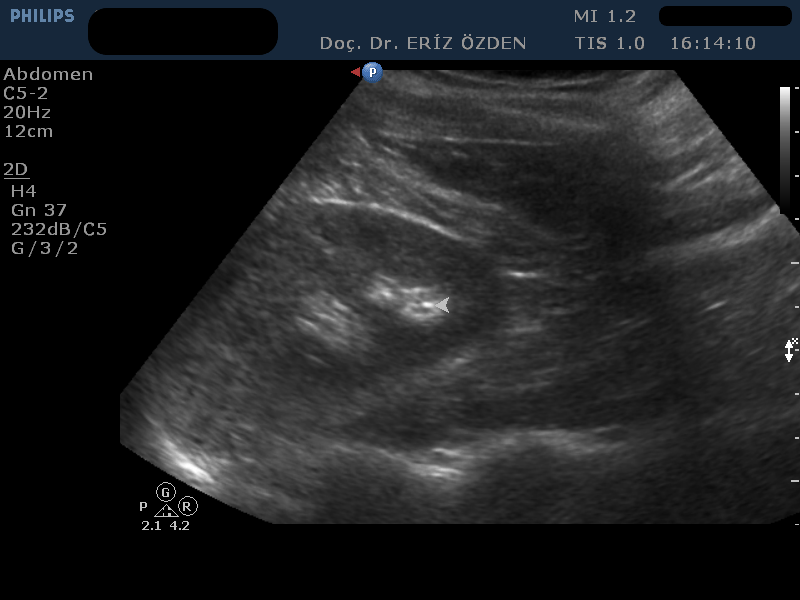

Böbrek Taşı Nasıl Tespit Edilir? Böbrek taşı ağrısı, tıpta bilinen en şiddetli ağrılardan birisidir. Genelde böbrek içinde sabit duran taşlar şiddetli ağrıya neden olmaz. Ancak taş böbrekten çıkıp, üreter adı verilen idrar kanalına girdiğinde şiddetli ağrı başlar. Kolik ağrısı denilen bu durumda ağrıyla birlikte bulantı, kusma gibi bulgular ve idrarda kan da görülebilir. Ayırıcı tanı öncelikle görüntüleme yöntemleriyle yapılır. Ağrının kaynağı idrar yollarındaki taş mı, taş varsa yeri neresi ve büyüklüğü nedir sorularının cevapları tedavide çok önemlidir. Bu bilgiler düz röntgen filmi, Bilgisayarlı Tomografi ya da Ultrason ile elde edilir. Böbrek taşlarının hepsi röntgen filminde görülmez. Bu tip taşlar kimyasal içerikleri nedeniyle röntgen ışınlarına geçirgendirler ve filmde hiç görülmezler. Direk röntgen filminin diğer bir dezavantajı ise hastanın az da olsa zararlı iyonize radyasyona maruz kalmasıdır. Ultrason ise hiç zararlı radyasyon içermeyen bir yöntemdir ve kimyasal içeriğinden bağımsız olarak hemen tüm böbrek taşları görülebilir. Ultrasonla izlenemeyen böbrek taşları boyutu 2 mm’den küçük olanlardır. Bunlar kristaloid odağı ya da kum olarak adlandırılır ve ancak idrar tahlillerinde mikroskop incelemesinde görülür. Böbrekten çıkıp kanala giren taşlarda ultrasonla hem taşı, hem de röntgende görülemeyen idrar kanalı genişlemelerini izleyebiliriz. Böylece, düşmesi geciken taşlarda, böbreğin durumuna göre ne kadar bekleneceğine karar verilebilir. Ultrasonun tek dezavantajı, bağırsak gazı çok yoğun olan hastalarda, kanal içindeki taşları görmenin zorluğudur. Üreter adını verdiğimiz kanalın içindeki taşlar, bağırsak gazlarının arkasında kaldıysa, ultrasonla görülemeyebilir. Uluslararası çalışmalarda üreter taşlarının ultrasonla görülebilme oranı %50 olarak bildirilmektedir. Ancak, ultrasonu yapan doktorun tecrübesi ve uzun zaman ayırarak sabırla taşı araması, kanaldaki taşların görülme oranını ciddi anlamda yükseltmektedir.

Üreter taşlarını en net gösteren yöntem ise Bilgisayarlı Tomografidir (BT). Hemen hemen tüm üreter taşları BT ile izlenebilir. Ancak tomografi çekimi sırasında hasta düz röntgen filminden daha da yüksek oranda zararlı radyasyon alacaktır. Bu yüzden, böbrek taşı ve üreter taşı varlığından şüphelenilen hastalarda ilk olarak Ultrason incelemesi yapılması, eğer taş ultrasonla görülemiyor ise düz röntgen filmi ya da BT’nin tercih edilmesi önerilmektedir.